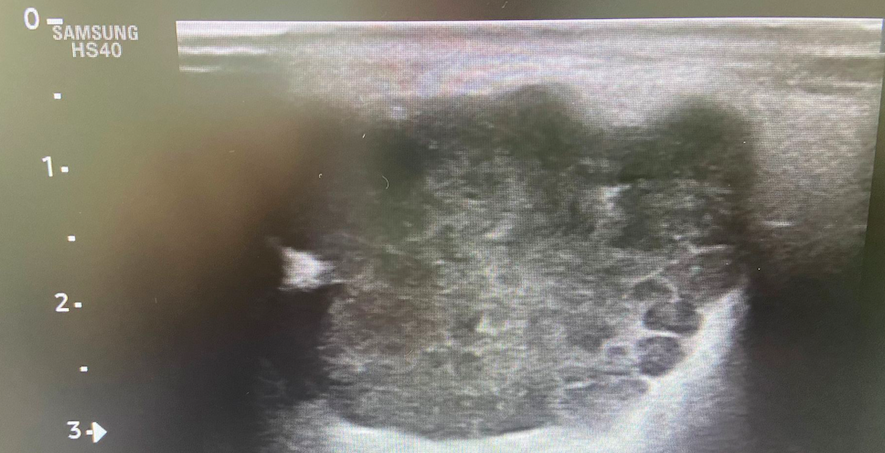

PC: Ecografía clínica en consulta: se identifica en ángulo mandibular izquierdo una lesión nodular bien delimitada, de morfología ovalada, heterogénea, de aproximadamente 28 × 39 mm, con ligera captación Doppler.

Hallazgos ecográficos